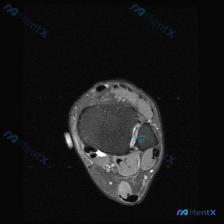

这是一张踝关节上方轴位T2序列MRI,用户的疑问是:图像中是否能观察到软组织积液?

- 骨骼结构:胫骨、腓骨远端骨皮质连续,骨髓信号正常,下胫腓联合韧带清晰,没有信号增高或连续性中断

- 肌腱结构:胫后肌腱、趾长屈肌腱、踇长屈肌腱、腓骨长短肌腱、跟腱形态都连续,信号均匀低信号,没有腱鞘积液、肌腱增粗或肌腱内异常高信号

- 关节与软组织:关节间隙内没有明显病理性积液高信号,周围皮肤皮下也没有弥漫性水肿或血肿

- 病变排查:胫骨前方内侧、腓骨外侧都没有占位性病变或异常信号区

整体来看,这张图像展示的解剖结构信号都是正常的,没有急性损伤、炎症的典型征象。

在这张特定的轴位层面图像上,没有发现符合病理性软组织积液典型表现(T2高信号聚集)的区域。